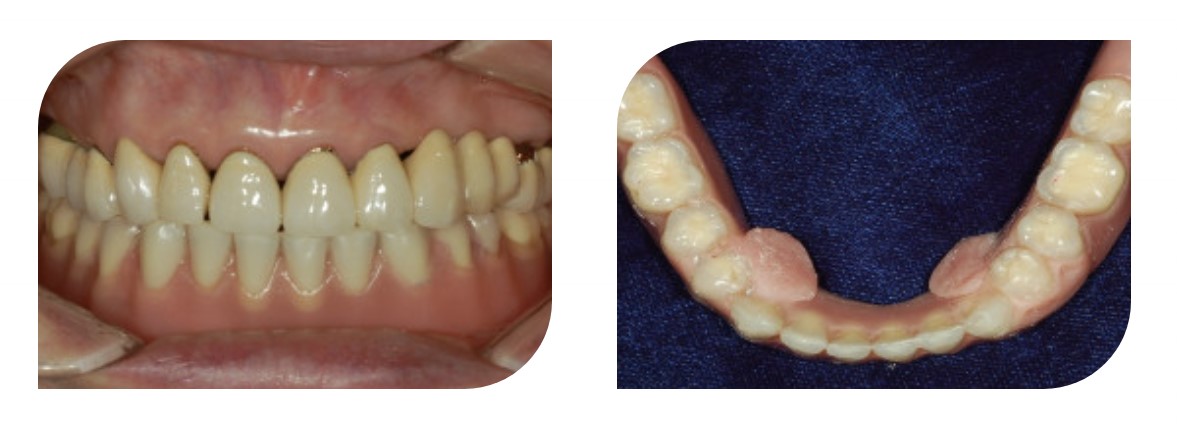

Финальный съемный протез